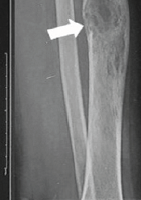

Figure 1: (a) Pre-operative radiograph reveals acute, mildly comminuted fractures of the mid/distal tibia and proximal fibular shaft. (b) Post-operative radiograph reveals intramedullary nailing of tibial shaft fracture in improved alignment and proximal fibular shaft fracture with increased displacement and apex posterior angulation. Upon the present presentation with the increased lateral calf pain and swelling, Doppler ultrasound revealed a large pseudoaneurysm of the ATA with the characteristic yin-yang sign (Fig. 2). CTA confirmed a pseudoaneurysm arising from the proximal ATA, surrounded by a large hematoma in the leg (Fig. 3). The largest aneurysmal sac measured approximately 8.7 × 10.4 × 16.1 cm, with an actively filling, non-thrombosed component measuring about 3.4 × 3.8 × 6.5 cm. Given the significant compressive symptoms caused by the hematoma, coil embolization of the ATA was performed to exclude blood flow into the pseudoaneurysm cavity. Selective catheterization of the left ATA was achieved through ultrasound-guided puncture of the right common femoral artery. Multiple Penumbra Ruby coils were deployed into the proximal and distal segments of the ATA, effectively sealing the pseudoaneurysm defect. A pre- and post-procedural angiogram demonstrated successful cessation of blood flow into the pseudoaneurysm cavity (Fig. 4a and b).

Figure 2: Color Doppler ultrasound shows a large, rounded structure with a classical yin-yang sign arising from the region of the anterior tibial artery.